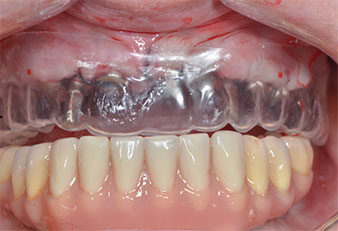

Compte tenu de la dureté relative de l’os (D2) à cet endroit, les sites recevant des implants de 10mm de long aux régions 11 et 21 ont été finalisés à l'aide d’une fraise de 4mm de diamètre, associée à un contre-angle chirurgical W&H WS-75 L, au moteur d'implantologie Implantmed de W&H ainsi qu’au module Osstell ISQ de W&H. En revanche, en raison de leur structure osseuse molle, les sites postérieurs ont été préparés en vue de l’obtention d’un diamètre final de 3mm à l'aide de l’insert Piezomed I3P. Les implants ont enfin été posés par voie transgingivale (Flap Less) pour obtenir l’ostéointégration dans un délai de trois mois (Figures 6-10). L'appareil existant a été maintenu sur quatre implants provisoires (Fig. 8).